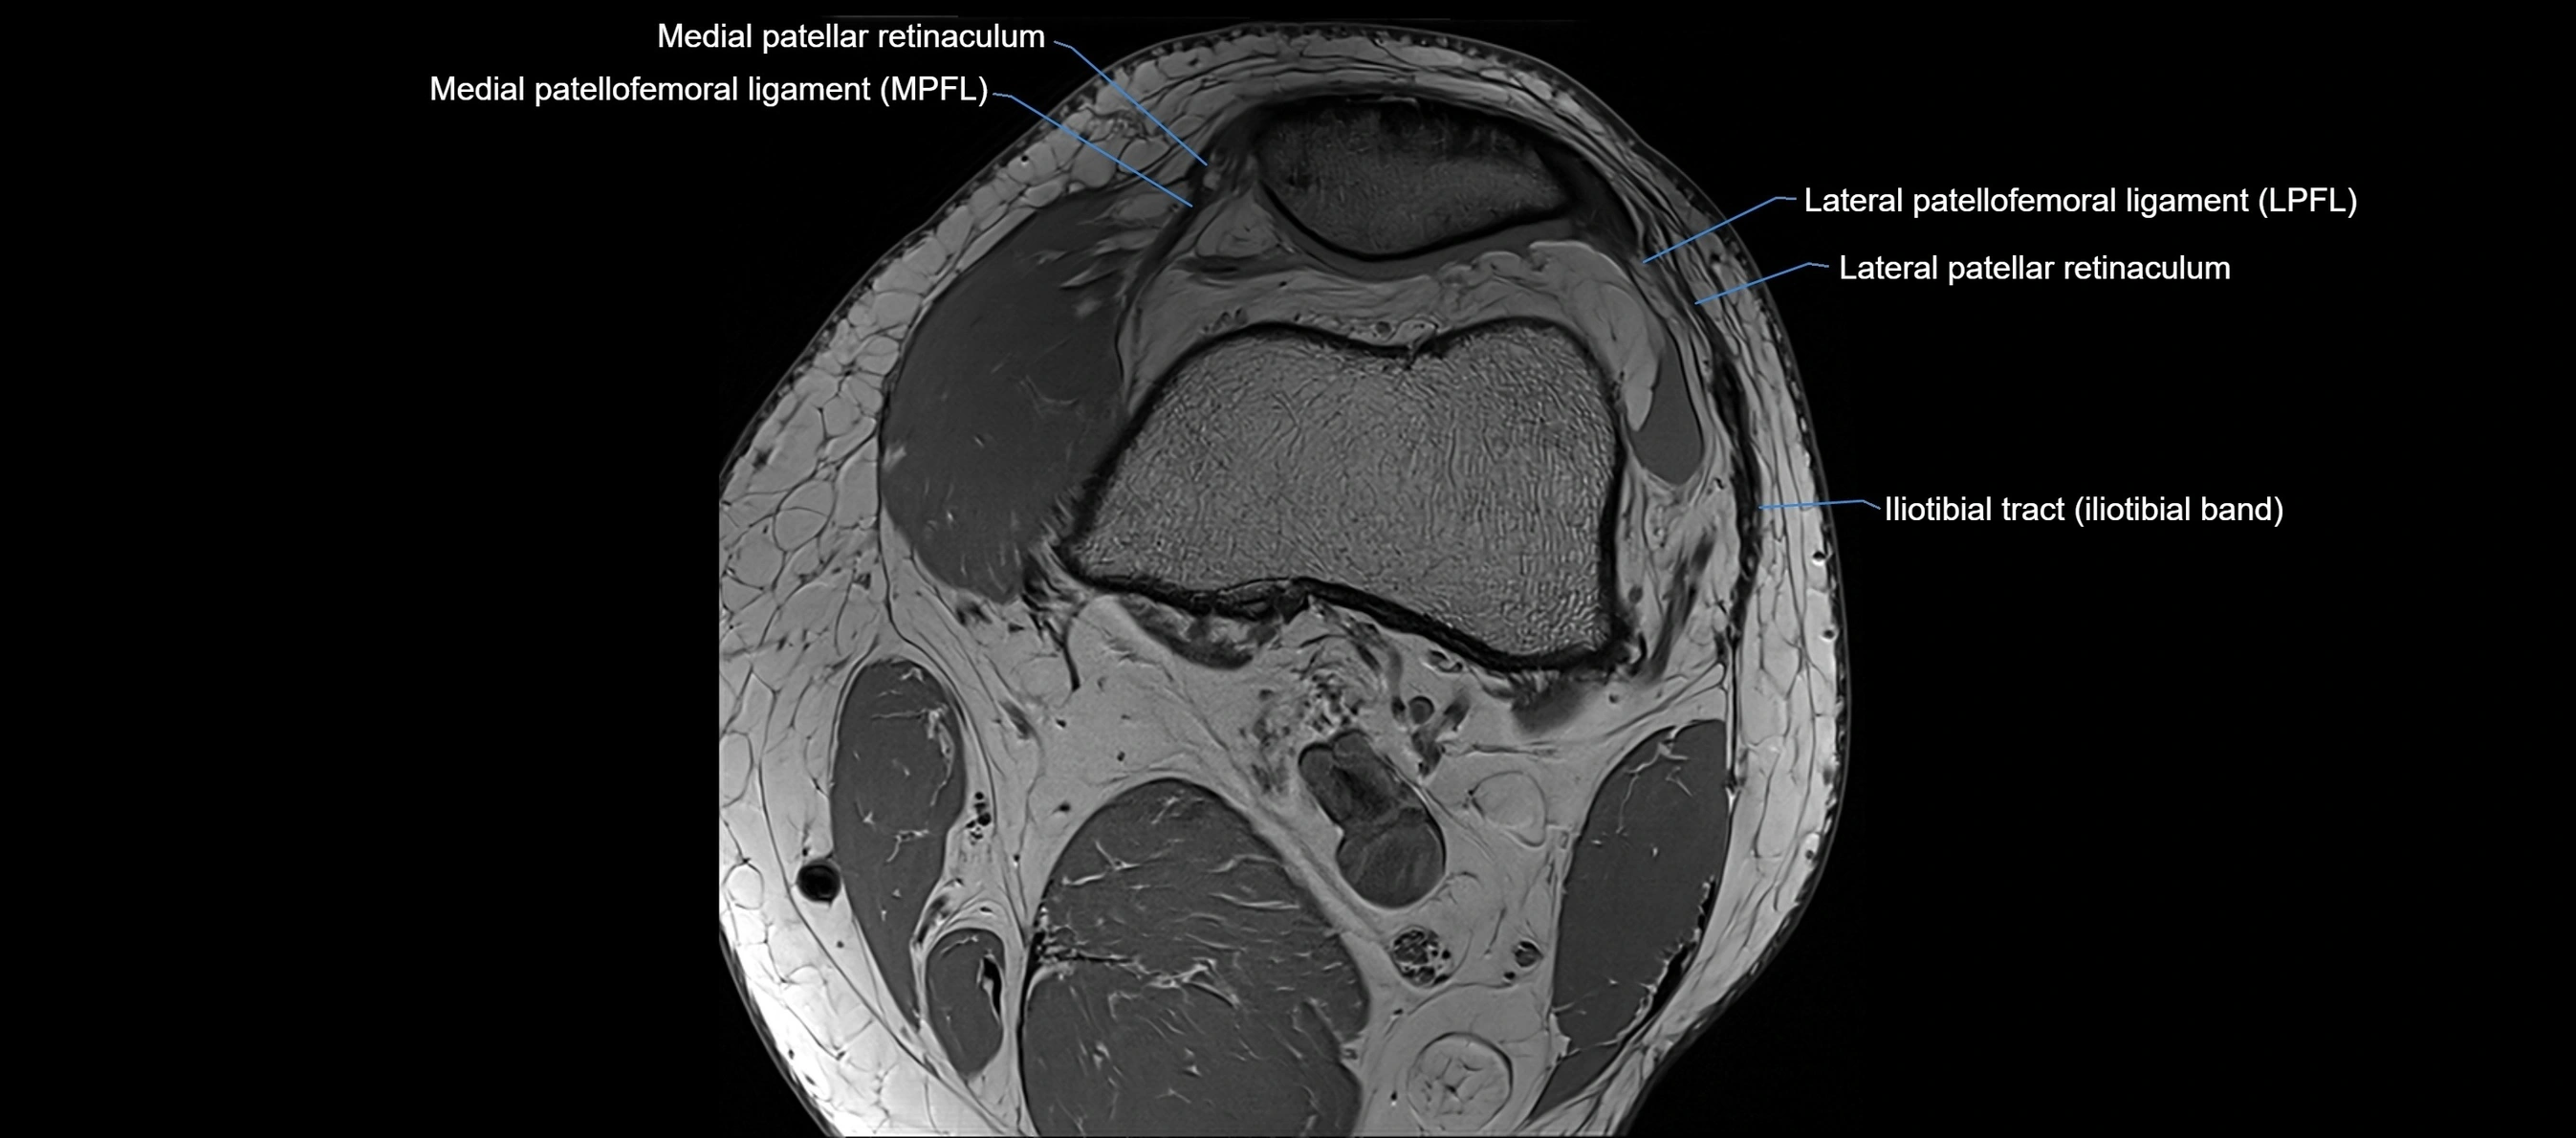

MRI images

image